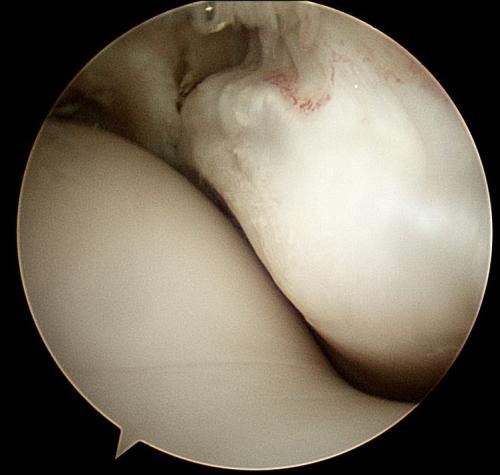

A rehabilitation program will be provided for your horse. This may also include suggestions for post-surgical treatments. For example, it is routine to perform Hyaluronic acid/corticosteroid injections at 2 weeks post surgery following arthroscopic chip/fragment removal. When there is substantial soft-tissue or cartilage injury, we often recommend biologic therapies.